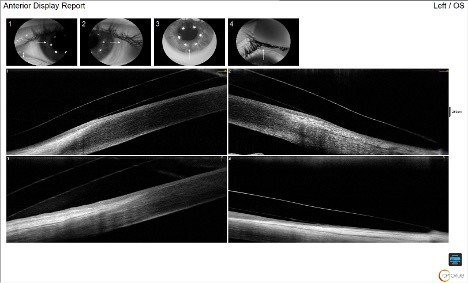

Based on the findings of a diagnostic scleral lens fitting, a trial lens was ordered. To improve the accuracy of the fit, anterior segment optical coherence tomography (OCT) technology (Optovue Solix, Visionix, USA) was utilized in conjunction with slit lamp examination to evaluate the central clearance, limbal clearance, and edge alignment. Slit lamp evaluation of the initial trial lens revealed an adequate central clearance with no areas of central touch, inferior decentration with thin limbal clearance superiorly and excessive limbal clearance inferiorly, and slightly flat edge alignment both temporally and superiorly. When evaluated via OCT imaging, the central clearance was measured to be 222 µm as seen in Figure 2. The superior limbal zone was clearing adequately, while the inferior limbal zone showed excessive clearance.

The excessive inferior clearance was not concerning, as there were no signs of conjunctival swelling or prolapse on OCT (see Figure 3) and no limbal hyperemia on slit lamp examination. Good edge alignment was found at 360º, showing conjunctiva covering half of the lens edge thickness on OCT. The trial was dispensed to the patient, and a follow-up exam was completed 1 week later. At the follow-up appointment, after 5 hours of lens wear, the central clearance was 205 µm, the limbal zone showed no change, and no conjunctival prolapse was found inferiorly in the area of excessive limbal clearance. The edge alignment was improved superiorly and temporally, no blanching was present on slit lamp evaluation, and the patient reported no foreign body sensation. The lens was removed, and sodium fluorescein stain was instilled. No staining or impression ring pooling were present on the cornea or conjunctiva. The scleral lens prescription was finalized, and the patient was instructed to return to care in 6 months for a scleral lens progress examination and possible fitting of the right eye.

Anterior segment OCT can be an invaluable tool to assist with scleral lens fitting and improve lens accuracy and alignment. This straightforward scleral lens fitting case demonstrates the ease of scleral lens fitting with OCT assistance. Several Optovue Solix scan protocols can be useful, including Corneal Mapping (full corneal epithelial, stromal, and pachymetry mapping), to achieve corneal topography and select the initial diagnostic lens. FullRange AC, which can capture the entire anterior chamber in a single scan, can help image the central and limbal zones, and the Cornea Angle scan, which quantifies the openness of the iridocorneal angle, is useful for a more magnified limbal zone image as well as edge alignment.